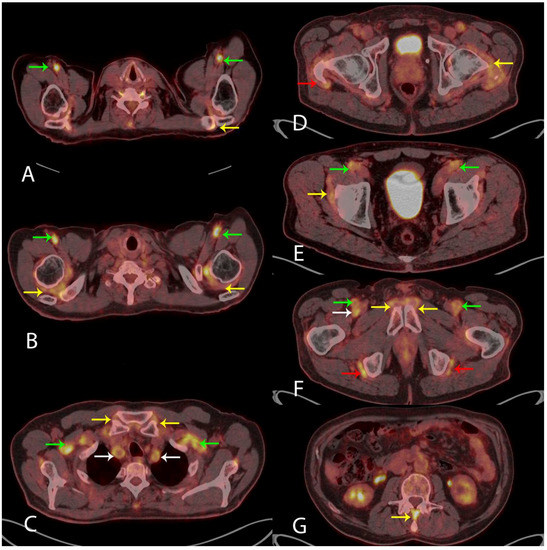

Visually measuring the 18F-FDG uptake in nine anatomical sites when evaluating the PET/CT scan for the diagnosis of PMR has been suggested [5,6]. These sites include: acromioclavicular joints (A) axial fused PET/CT (yellow arrow, left side shown), the high 18F-FDG uptake in the axillary arteries indicates LVV (green arrows); shoulder joints (B) axial fused PET/CT (yellow arrows), LVV in axillary arteries (green arrows); sternoclavicular joints (C) axial fused PET/CT (yellow arrows), LVV in subclavian arteries (green arrows) and common carotid arteries (white arrows); hip joints (D) axial fused PET/CT (yellow arrow, left side shown) and greater trochanter (D) axial fused PET/CT (red arrow, right side shown); the two iliopectinal bursae (E) axial fused PET/CT (yellow arrow, right side shown), LVV in common femoral arteries (green arrows); two symphysis pubis enthesis (F) axial fused PET/CT (yellow arrows) and two ischial tuberosities (F) axial fused PET/CT (red arrows), LVV in superficial femoral arteries (green arrows) and right profound femoral artery (white arrow); and interspinous ligaments (G) axial fused PET/CT (yellow arrow), respectively. The specificity of 18F-FDG PET/CT in the diagnosis of PMR is 95% given that the 18F-FDG uptake is above the uptake in the liver in ≥6 anatomical sites [5]. In our case, the 18F-FDG uptake met this criterion in all nine anatomical sites (not quantitatively shown). No malignancy was visualized. Based on the clinical information and the results of the 18F-FDG PET/CT, the patient was treated with 60 mg of Prednisolone resulting in the normalization of blood tests and rapid remission of symptoms. Our case shows that 18F-FDG PET/CT is a strong supportive imaging tool in the diagnosis of PMR and LVV. 18F-FDG PET/CT can be used where malignancy is a differential diagnosis, as proposed in the newest European League Against Rheumatism (EULAR) recommendations [7].